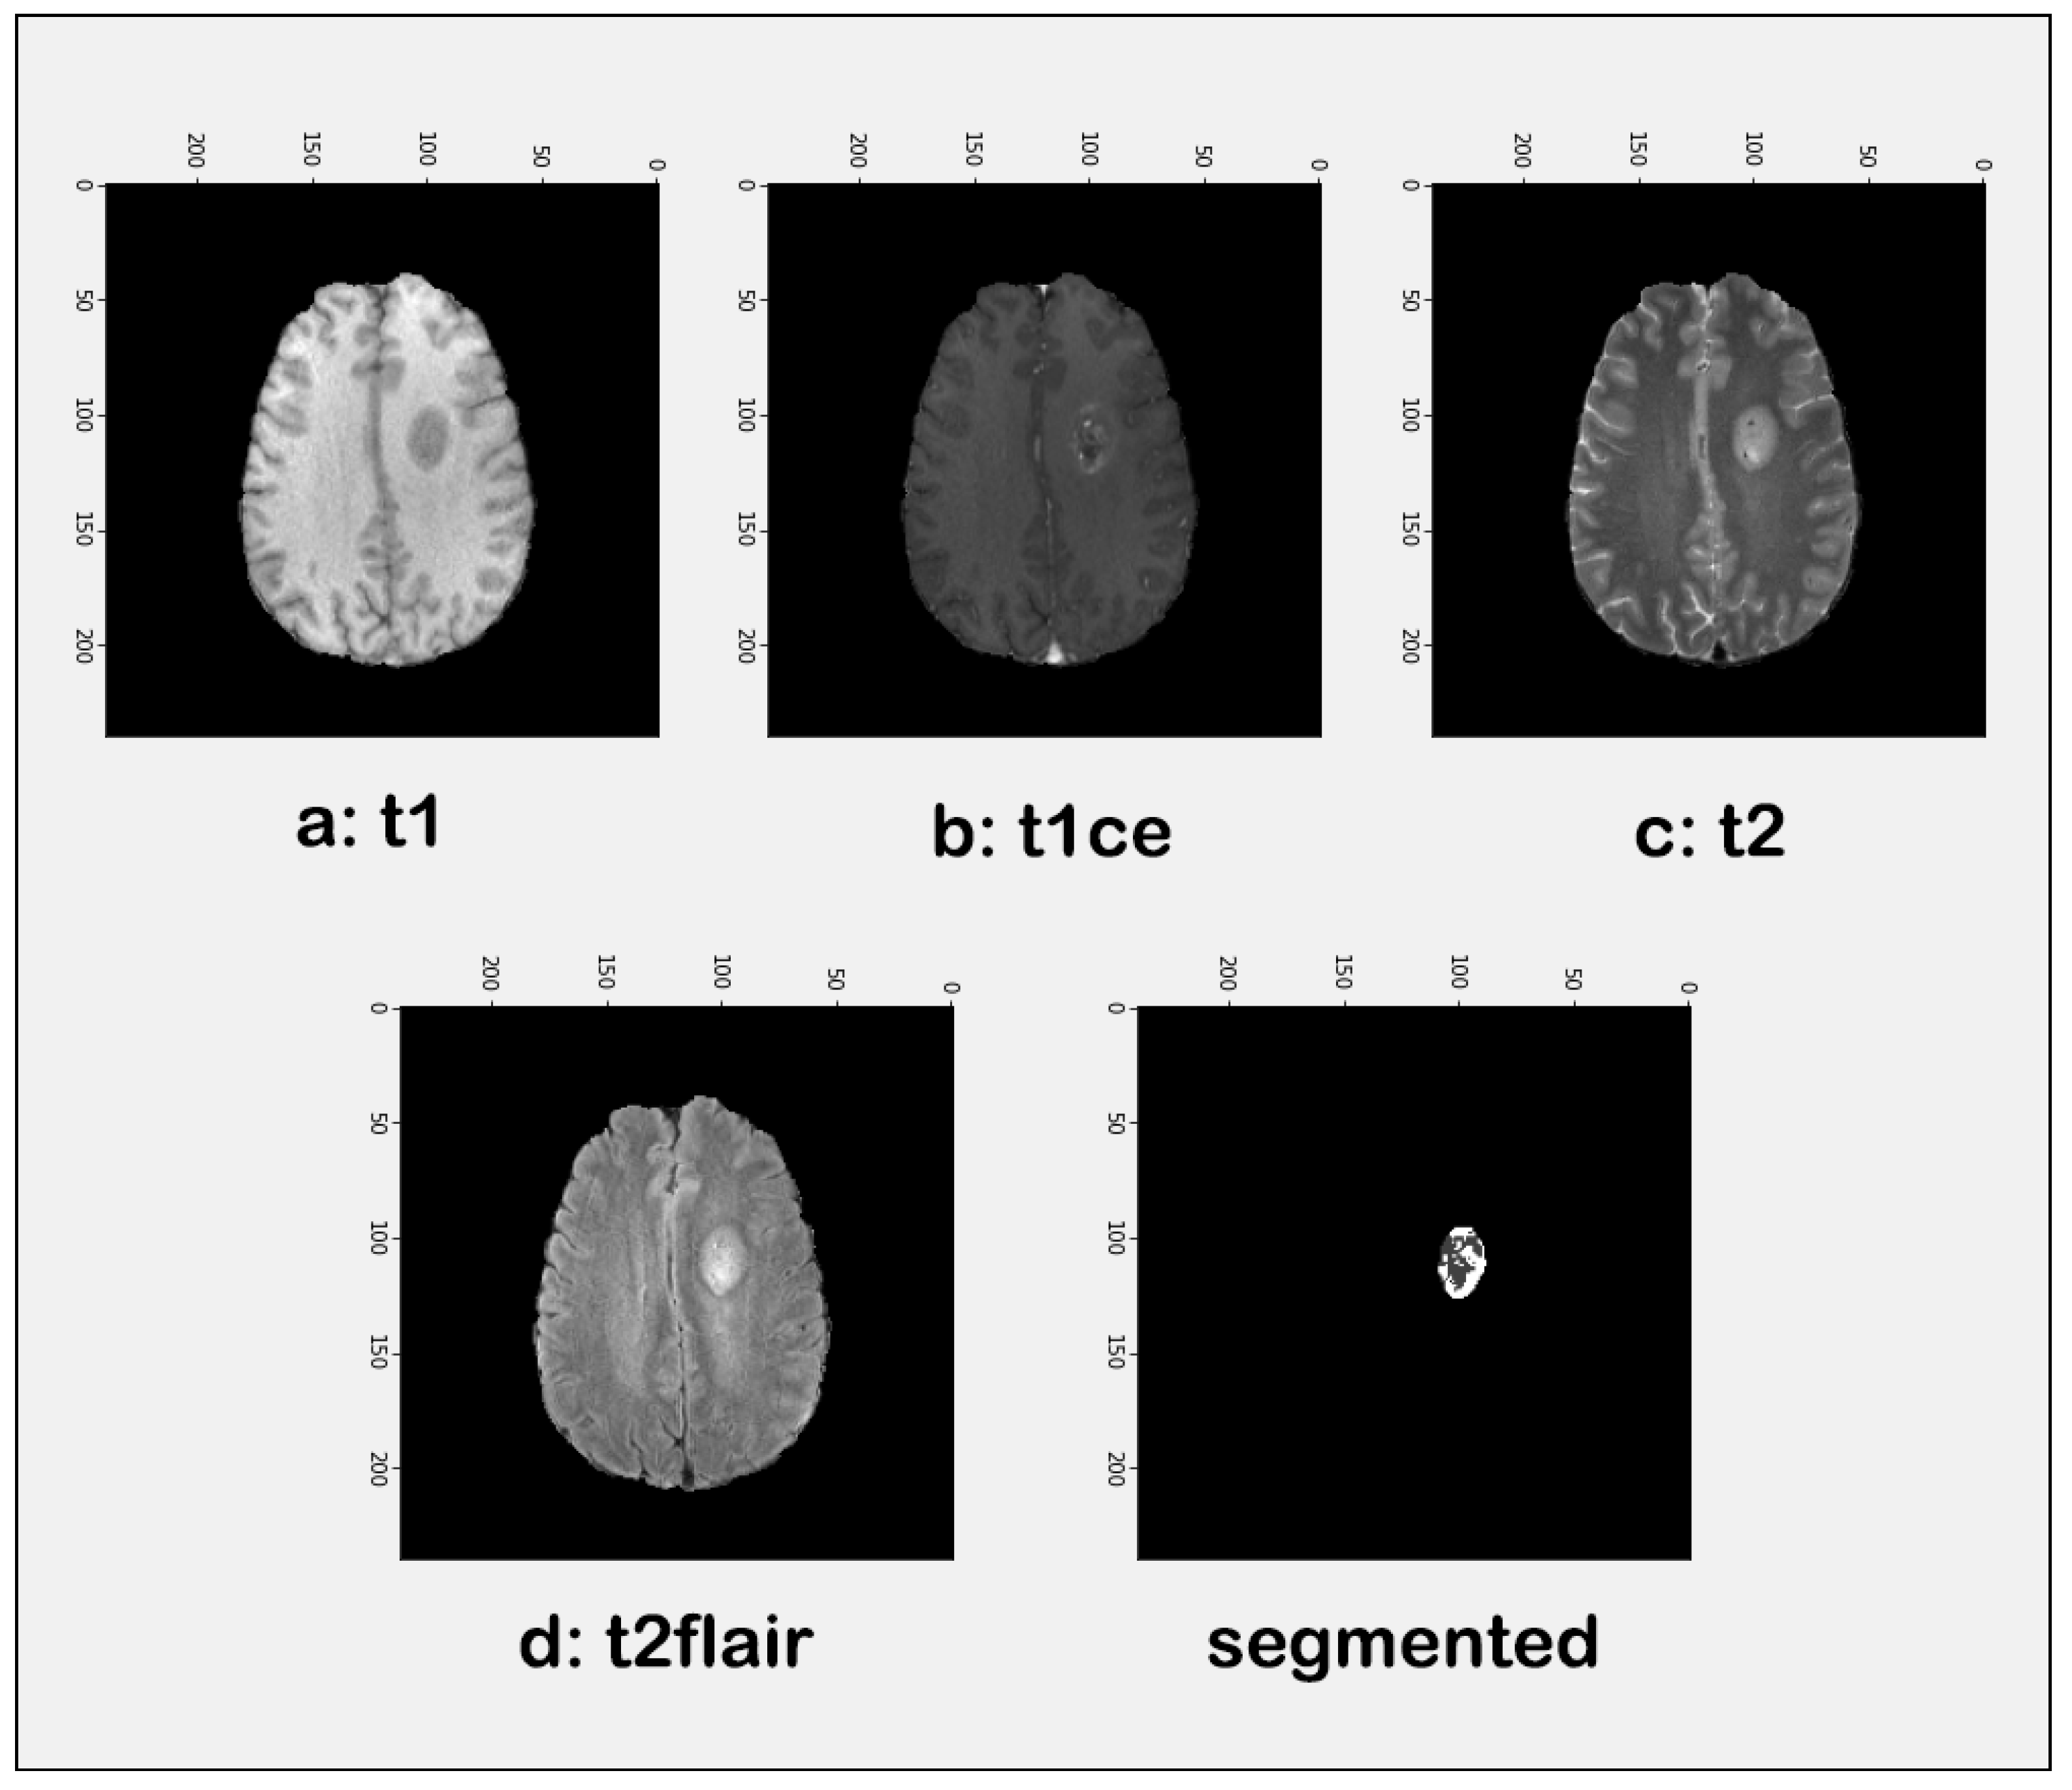

3.1. Pre-Processing

3.2. Tumor Identification

| Modality | Accuracy | Precision | F1 Score |

|---|---|---|---|

| T1 | 94.00 | 93.81 | 95.77 |

| T1ce | 94.00 | 93.81 | 95.77 |

| T2 | 94.38 | 93.62 | 95.65 |

| Flair | 93.23 | 93.81 | 95.77 |

| Segmented | 94.38 | 93.81 | 95.77 |

| Average | 94.20% | 93.77% | 95.75% |